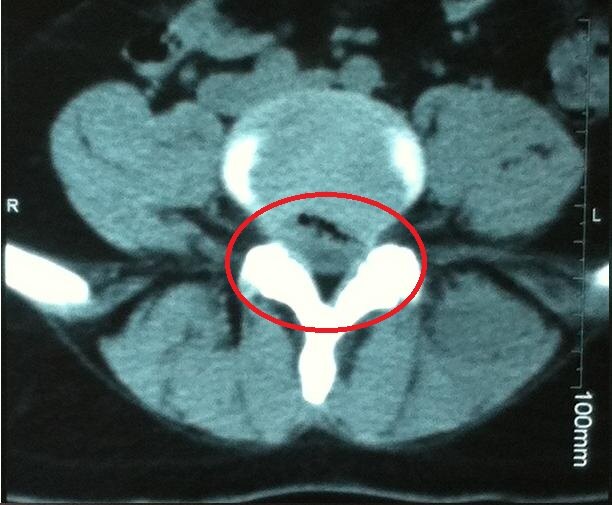

滕州市中心人民医院完成首例UBE脊柱内镜下腰椎微创融合手术脊柱内镜下腰椎微创融合手术。患者,男,45岁,因“右下肢疼痛麻木半年,加重半个月”收住院。入院后经全面检查,诊断为腰椎间盘突出症(L4/5... 它借助天然解剖间隙建立微创工作通道,解除神经压迫,对椎旁肌肉损伤较小,且能够最大程度地保留完整的脊柱结构,维持了术后脊柱的稳定,具有...